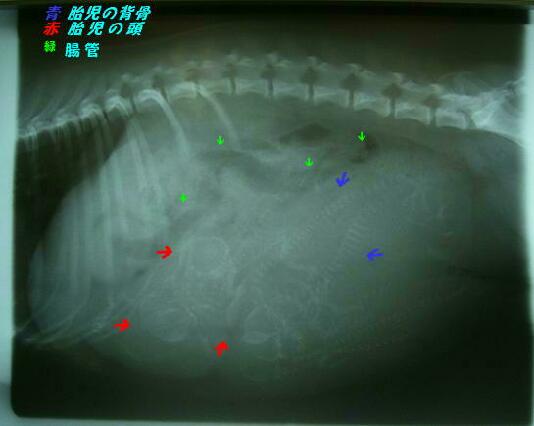

日頃、レントゲンには見慣れたお父さんが

牡丹のレントゲンを何度も見て

絶対に3頭ではないぞという。

しかし画質が悪すぎて何頭か分からないという。

レントゲンは2方向から2枚撮りました。

昨日のレントゲンは何だった?

と思う程鮮明な画像でハッキリと

5頭確認

しました。

そして、エコーでも心臓の動きをしっかり確認してきました。